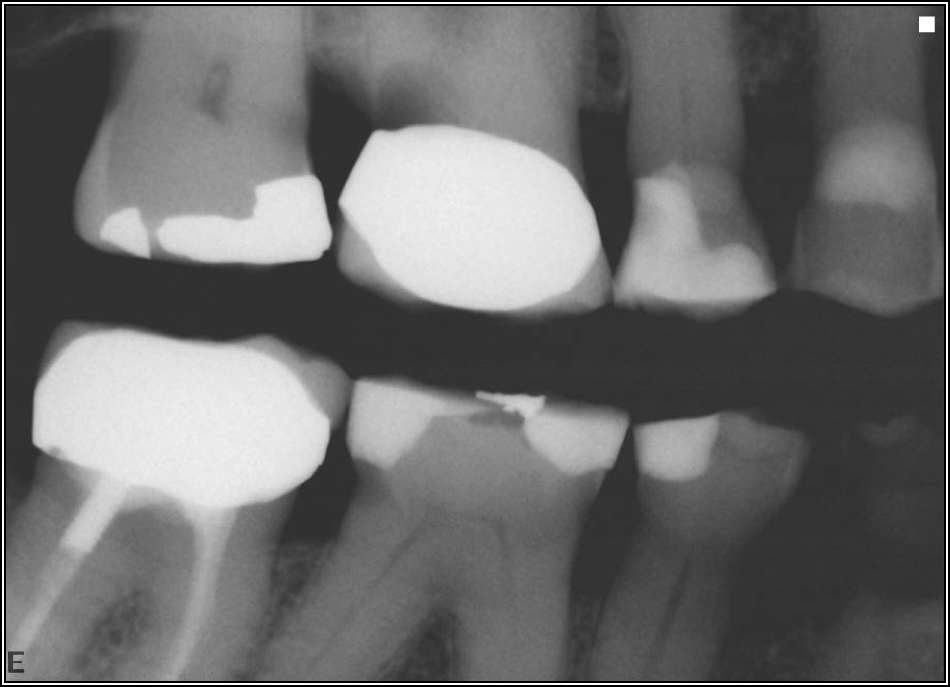

If a tooth stands alone, greater forces will be placed on it because it has no adjacent teeth to provide support. This situation will affect the decision-making process for placing a post. Figure 3 shows a tooth that was on an island and would be having three implants placed in front of it. The tooth would take a much greater beating than another tooth that had support proximally. Even though it had a good root canal, the clinician would need to account for whether the tooth would last until the implants integrated. Figure 4 shows a case that would quickly proceed to implants. The patient had a less-than-ideal bridge for over a decade, with decent endodontics and functionality. There was also an overhang on the premolar. The post was not ideal in this case because there was one distal canal and not all the gutta-percha was removed from it. An intimate fit should be the goal with the post and the walls. Whether using a threaded or non-threaded post, there should not be excess gutta-percha because it is not as solid as the tooth and will lead to greater movement. That movement on the tooth and bridge will create too much force and result in demise.

Fig 4. Case that quickly would proceed to implants.

Figure 4